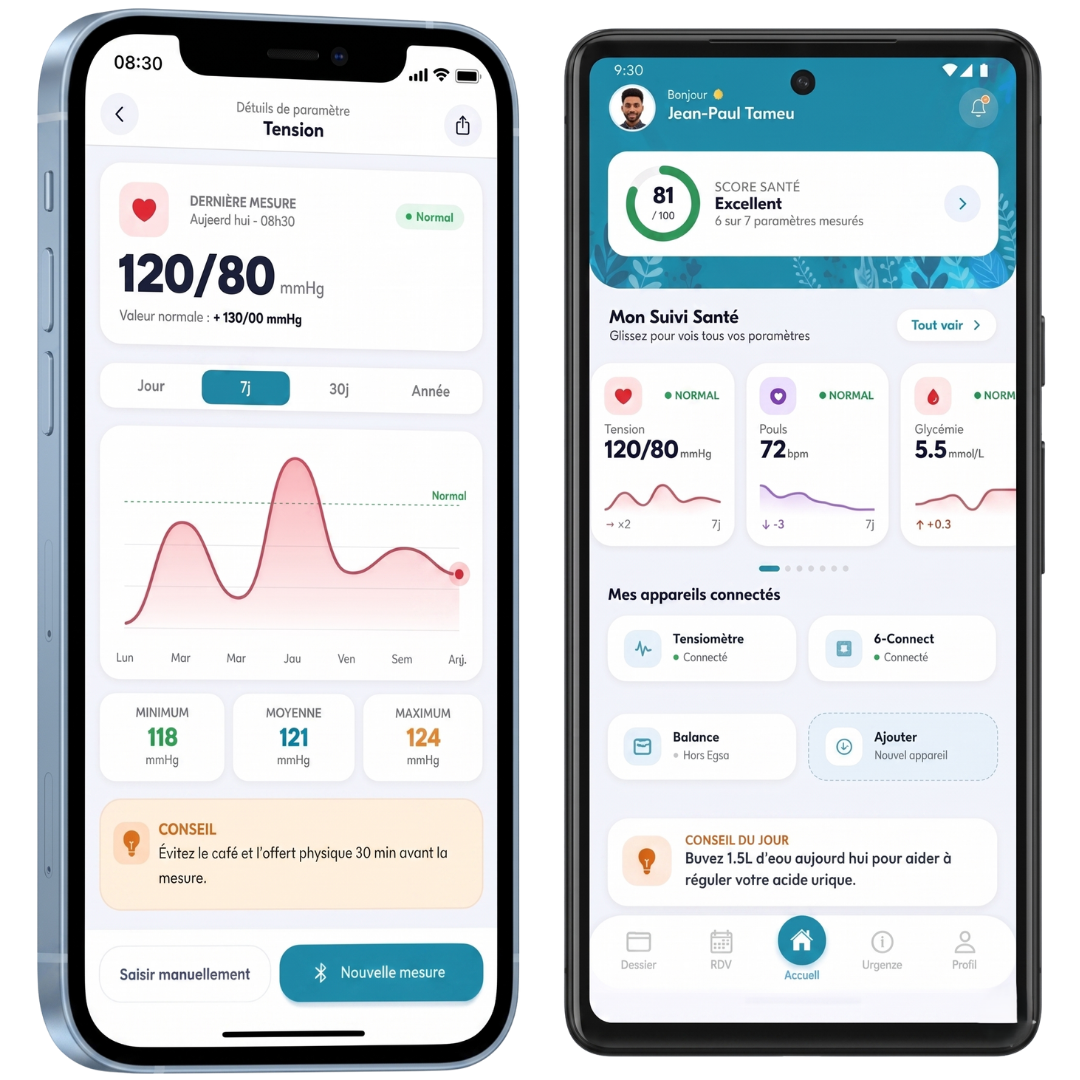

Mon suivi

santé

Votre santé dans votre poche. Accédez à tous nos services où que vous soyez : prise de rendez-vous, suivi médical et bien plus encore.

- Suivi complet de vos paramètres vitaux

- Analyse intelligente de votre score de santé

- Conseils personnalisés et suivi quotidien

- Gestion de vos appareils de santé connectés